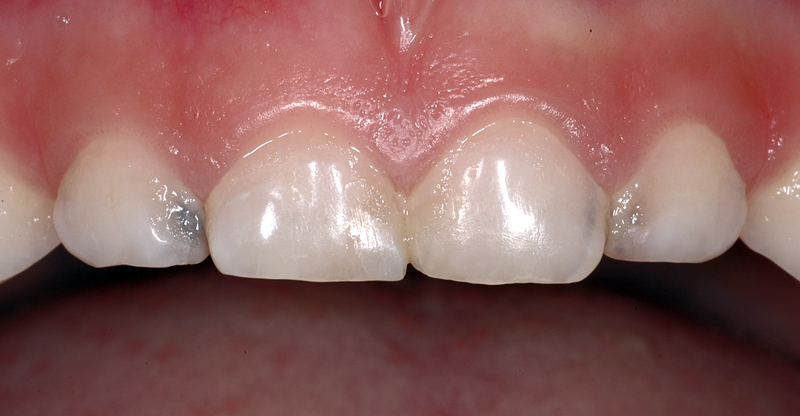

In diesem Beispiel ist ein «weisser» Fleck auf dem rechten oberen Schneidezahn (Zahn 11) einer 7-jährigen Patientin zu sehen. Solche Flecken sieht man häufig, z.B. wenn im Kleinkindalter ein Sturz auf die Milchzähne erfolgt ist und dabei die Wurzeln der Milchzähne die Zellen, die den bleibenden Zahn bilden, in Ihrer Funktion beschädigen. Aber auch andere Ursachen sind möglich, meist lässt sich aber nicht genau sagen, weshalb der Fleck entstanden ist.

Der Zahn ist allerdings, abgesehen von einer ästhetischen «Einbusse», vollkommen in Ordnung und braucht keine Therapie. Ästhetische Korrekturen sind möglich, sie werden individuell nach Bedürfnissen und Möglichkeiten geplant.

Im Bild sind zudem feine Querrillen auf den Zähnen zu sehen. Diese Rillen heissen Perikymatien und sind völlig «normal»

Sie sind vor allem an frisch durchgebrochenen, jungen Zähnen gut sichtbar. Die Ausprägung kann von Person zu Person verschieden stark sein.

Im Laufe des Lebens verflachen und verschwinden diese Rillen meist durch den Verlust von Zahnschmelz.

- Weisser Fleck auf dem rechten oberen Schneidezahn (Zahn 11) einer 7-jährigen Patientin